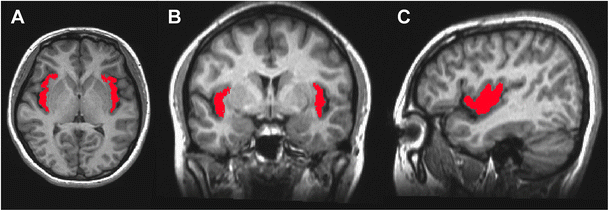

يعمل البرنامج العاطفي لوكالة المباحث في الغالب على ثلاثة اماكن في الدماغ.

يوجد اثنان من الهياكل في القشرة، حيث يحدث التفكير الواعي: القشرة الحزامية الأمامية (موجود في الصورة بالازرق )والقشرة الجزيرية(محدده بالأحمر).

كلاهما معنيان بتقييم العواطف للذات والآخرين. تكون هذه الهياكل أكبر قليلاً في النساء وأكثر نشاطاً أيضًا في النساء أثناء معالجة المعلومات الاجتماعية.

عندما تقوم النساء بمعالجة المحفزات الجنسية، تميل القشرة الحزامية الأمامية إلى الرد عبر تثبيط العاطفة، ربما كوسيلة تمنع وكالة المحققين من رد فعل المرأة تجاه محفز جنسي إلى أن يتم تقييمه بشكل صحيح.

تشارك كل من القشرة الجزيرية والحصين (او قرن آمون هو أحد المكونات الرئيسية لدماغ ) في تخزين واسترجاع الذكريات العاطفية، وكلاهما أكبر حجمًا وأكثر نشاطًا عند النساء منه عند الرجال.

والمنطقة الأخرى هي اللوزة الدماغية، الموجودة في القشرة الدماغية اللاواعية.

تقوم النساء بترميز العواطف من خلال اللوزة الدماغية اليسرى، بينما يقوم الرجال بمعالجة العواطف من خلال اللوزة اليمنى.

عند الرجال، يؤدي تنشيط اللوزة الدماغية اليمنى والنصف الأيمن من الكرة مخية إلى تعزيز الذاكرة لفهم الفكرة الرئيسية أو الجوهرية لتجربة أو حدث.

المثير للاهتمام، أنه على الرغم من أن اللوزة الدماغية اليمنى تنشط عند الرجال أثناء مشاهدة المواد الإباحية، إلا أنها ليست كذلك عند النساء.

إن اللوزة الدماغية اليسرى تنشط عند النساء أثناء معالجة الروايات المثيرة.